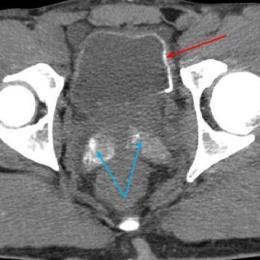

Cystite emphysémateuse

Une patiente de 89 ans, sans antécédent majeur, consulte aux urgences à la suite d’une chute accidentelle avec fracture...